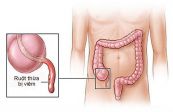

Viêm ruột thừa hay còn gọi là viêm ruột tịt. Đây là tình trạng ruột thừa bị viêm và nhiễm trùng. Bài viết dưới đây sẽ nói rõ hơn về triệu chứng, nguyên nhân và cách điều trị của bệnh, mời các bạn tham khảo!